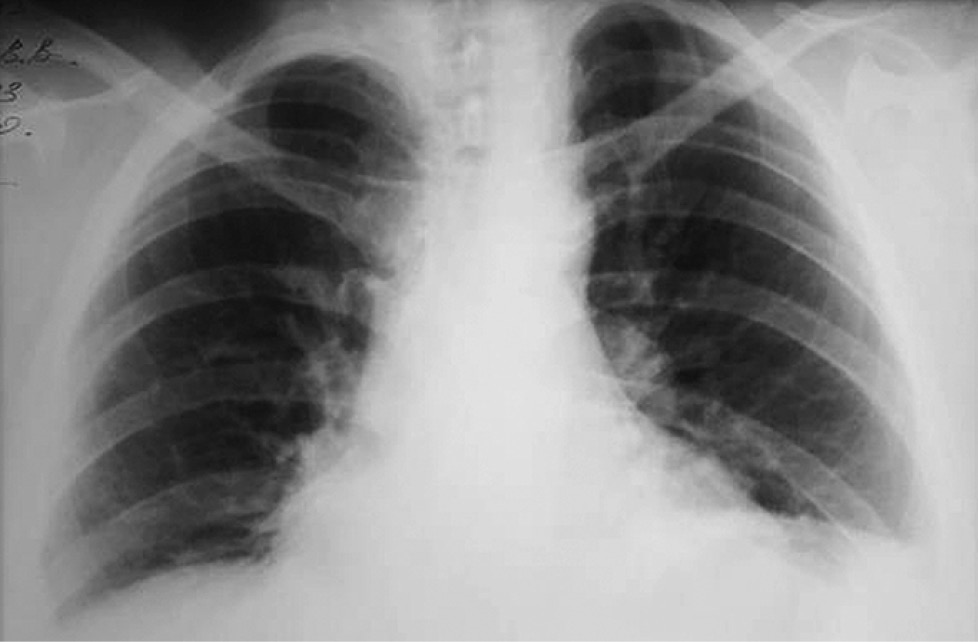

Из анамнеза известно, что больная в течение двух последних месяцев стала отмечать появление одышки при физической нагрузке. Состояние ухудшалось, дополнительно появились отёки на лице к вечеру. При обращении к участковому терапевту в поликлинику по месту жительства выполнена рентгенография грудной клетки, в результате выявлено массивное опухолевое образование в средостении (рис. 1, 2).

Рис. 2. Рентгенография грудной клетки в левой боковой проекции.

Fig. 2. Chest X-ray, left lateral view.